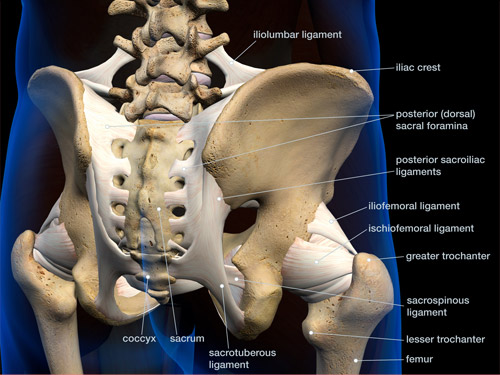

膀胱経をより効果的に流れを良くするためには、仙骨周囲の気門を開くことがポイントになります。イメージとしては、この場所に穴を開けるようにと意識しながらおこなうことで、気門が開きやすくなり、次に経穴を治療するときにより効果を発揮します。

ここでお伝えするのは、承扶(しょうふ)というポイントです。この経穴は臀部と大腿の境にあるお尻の溝の中央にあります。また、この場所は坐骨神経の走行する場所であり、解剖学的にも滞りやすい場所なのです。

胆経は斜角筋との関連がとても深いポイントです。もしこの経絡を使って斜角筋を緩めきることができれば、あなたは大腰筋や大殿筋で改善しない腰痛を治すことができます。斜角筋は第2の大腰筋と呼ばれ、腰からは離れていますが腰痛に関連が深い筋肉です。しかし、直接マッサージはしにくいですしマッサージでは緩まない筋肉です。そこでこの胆経を使うと簡単に緩めることができます。

胆経では、大転子直上の鬼門を開くことが重要です。イメージとしては、この場所に穴を開けるようにと意識しながらおこなうことで、気門が開きやすくなり、次に経穴を治療するときにより効果を発揮します。

経穴は中瀆(ちゅうとく)を狙っていきます。解剖学的な場所は膝窩より上方に行き、腸脛靱帯と大腿二頭筋のちょうど真ん中に位置します。

鼠径部

脾経では鼠径部の鬼門を開くことがポイントです。イメージとしては、この場所に穴を開けるようにと意識しながらおこなうことで、気門が開きやすくなり、次に経穴を治療するときにより効果を発揮します。